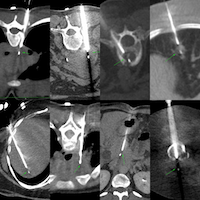

The patient came for a biopsy and I decided to use an anterior approach in the supine position.

Gun: 18G BARD, 20 mm throw, long

No of cores: 5 for HP

Position & Approach: Supine

Time Taken (marker to wash-out): 6 mins

Complication: 75 cc bleeding perisplenic stable after the 1st hour